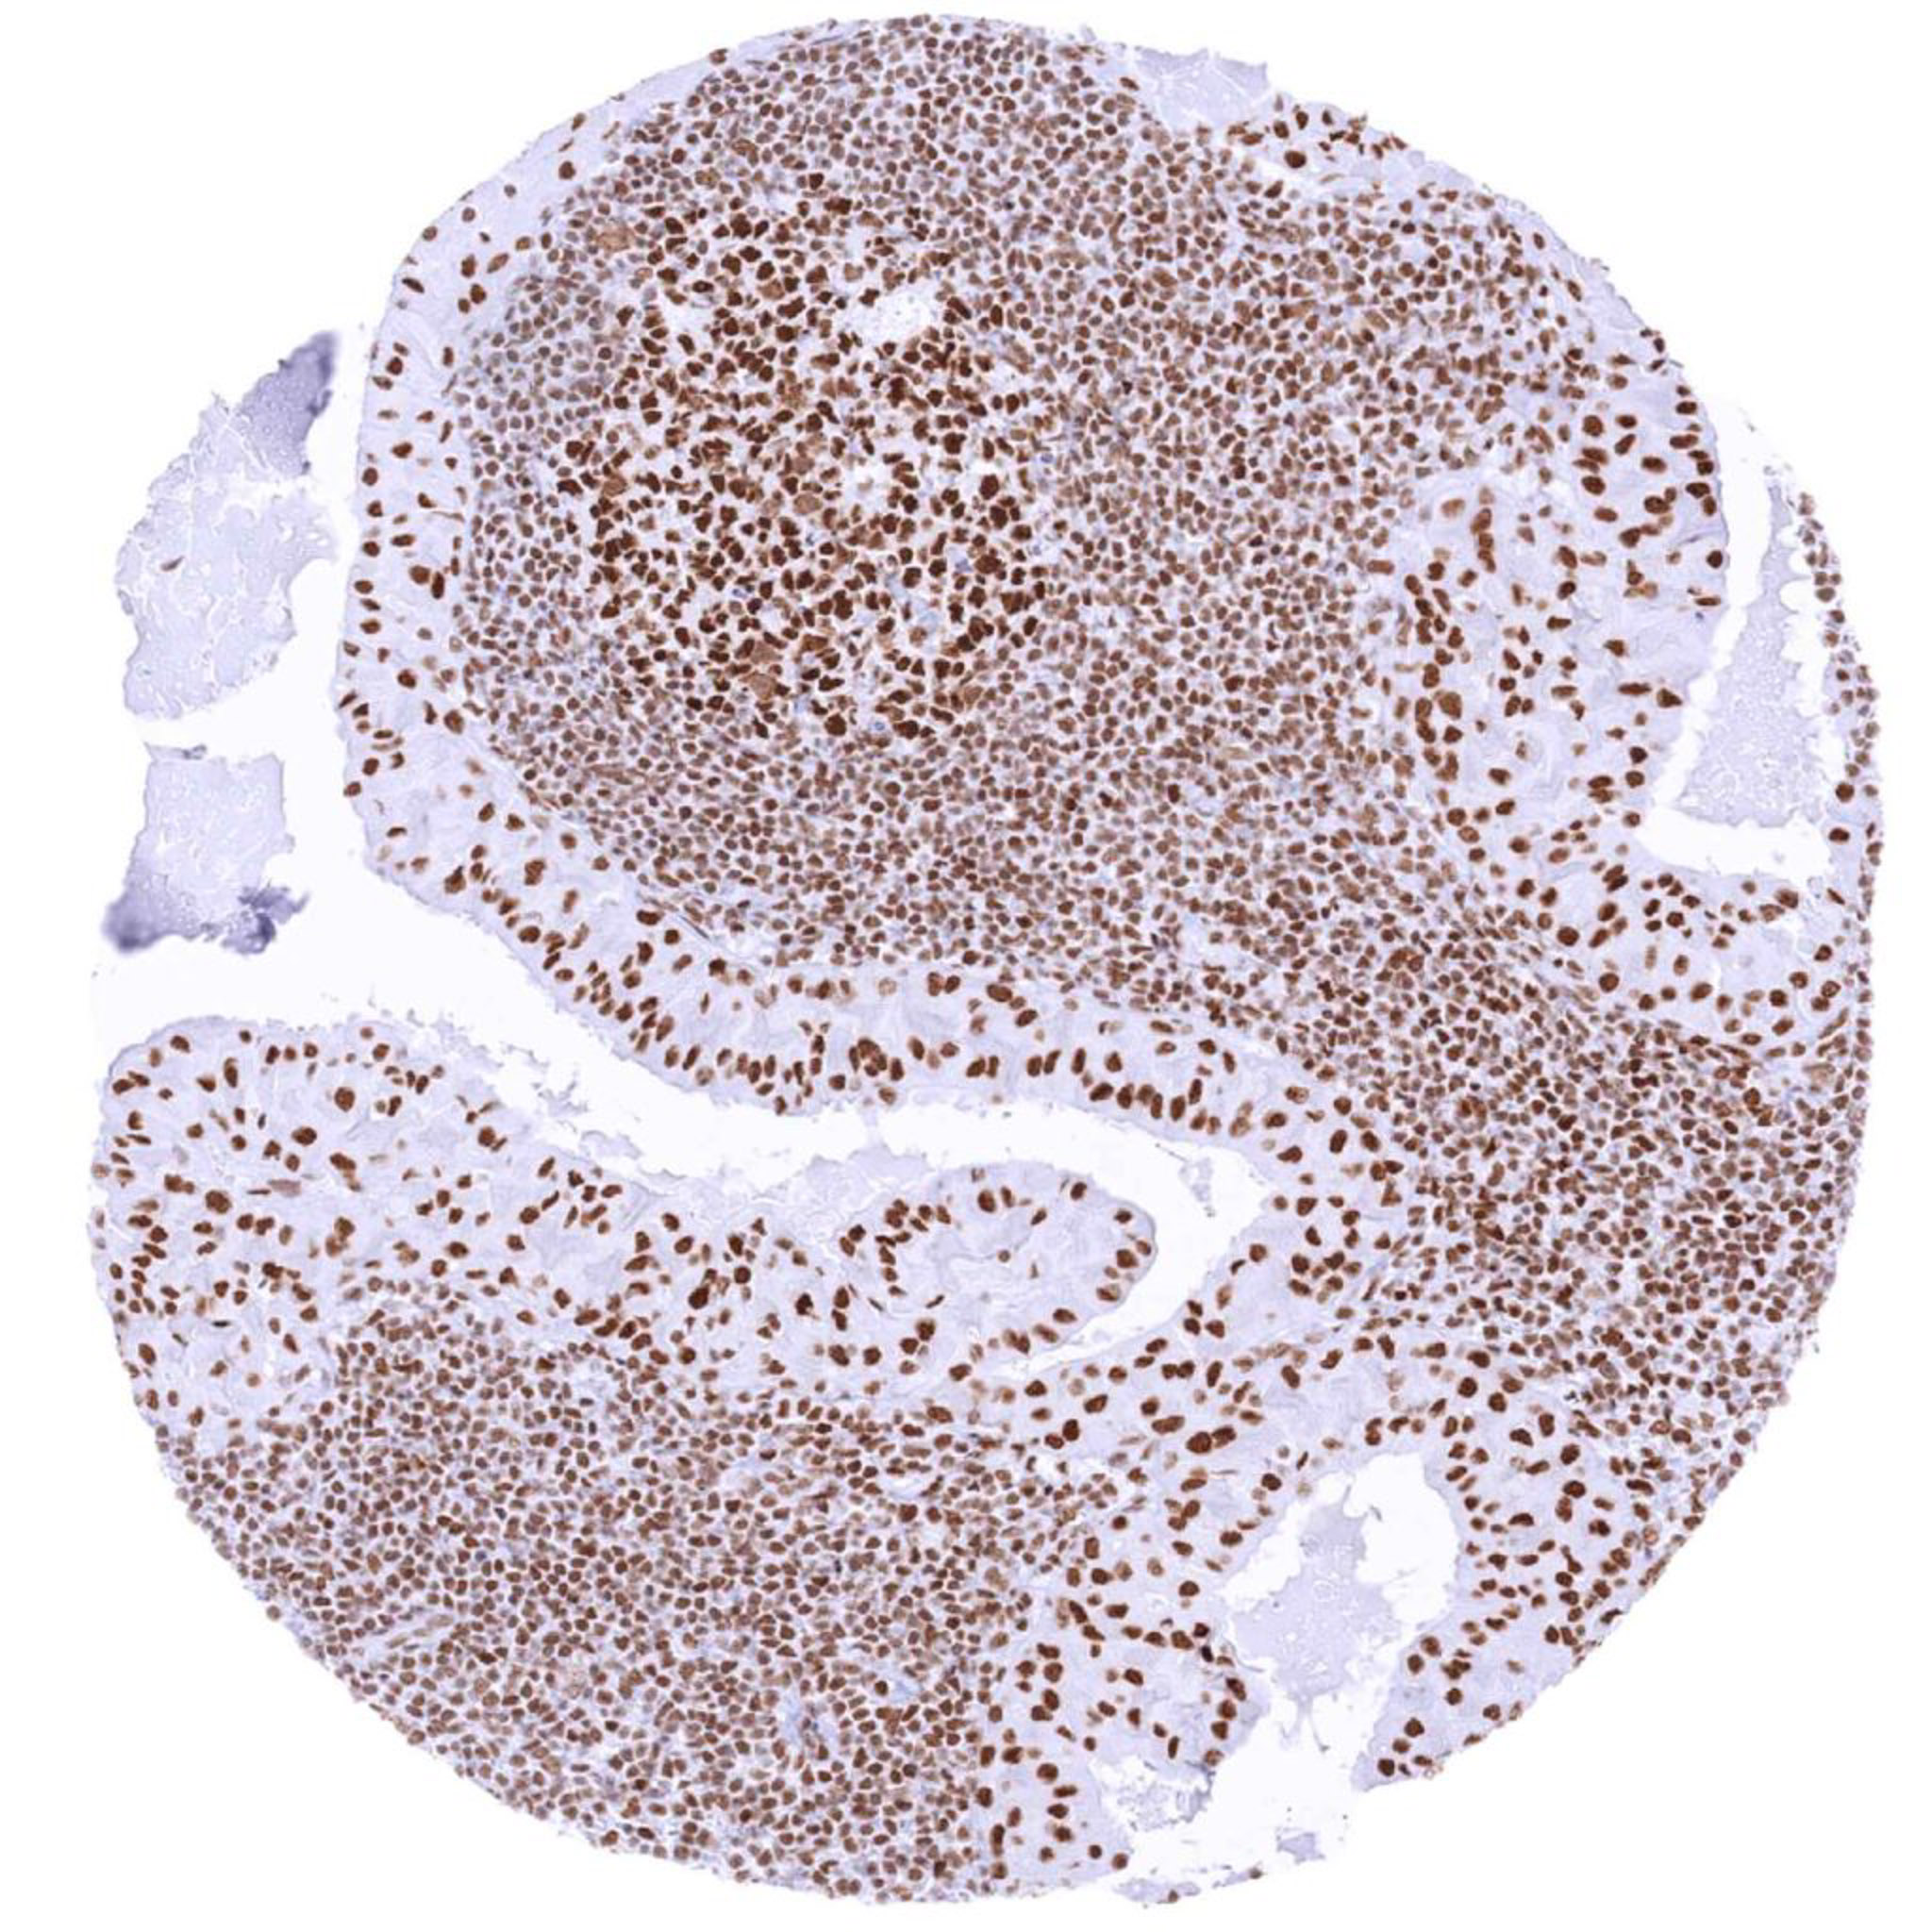

Testis – Seminoma with strong BRG1 staining of tumor cells